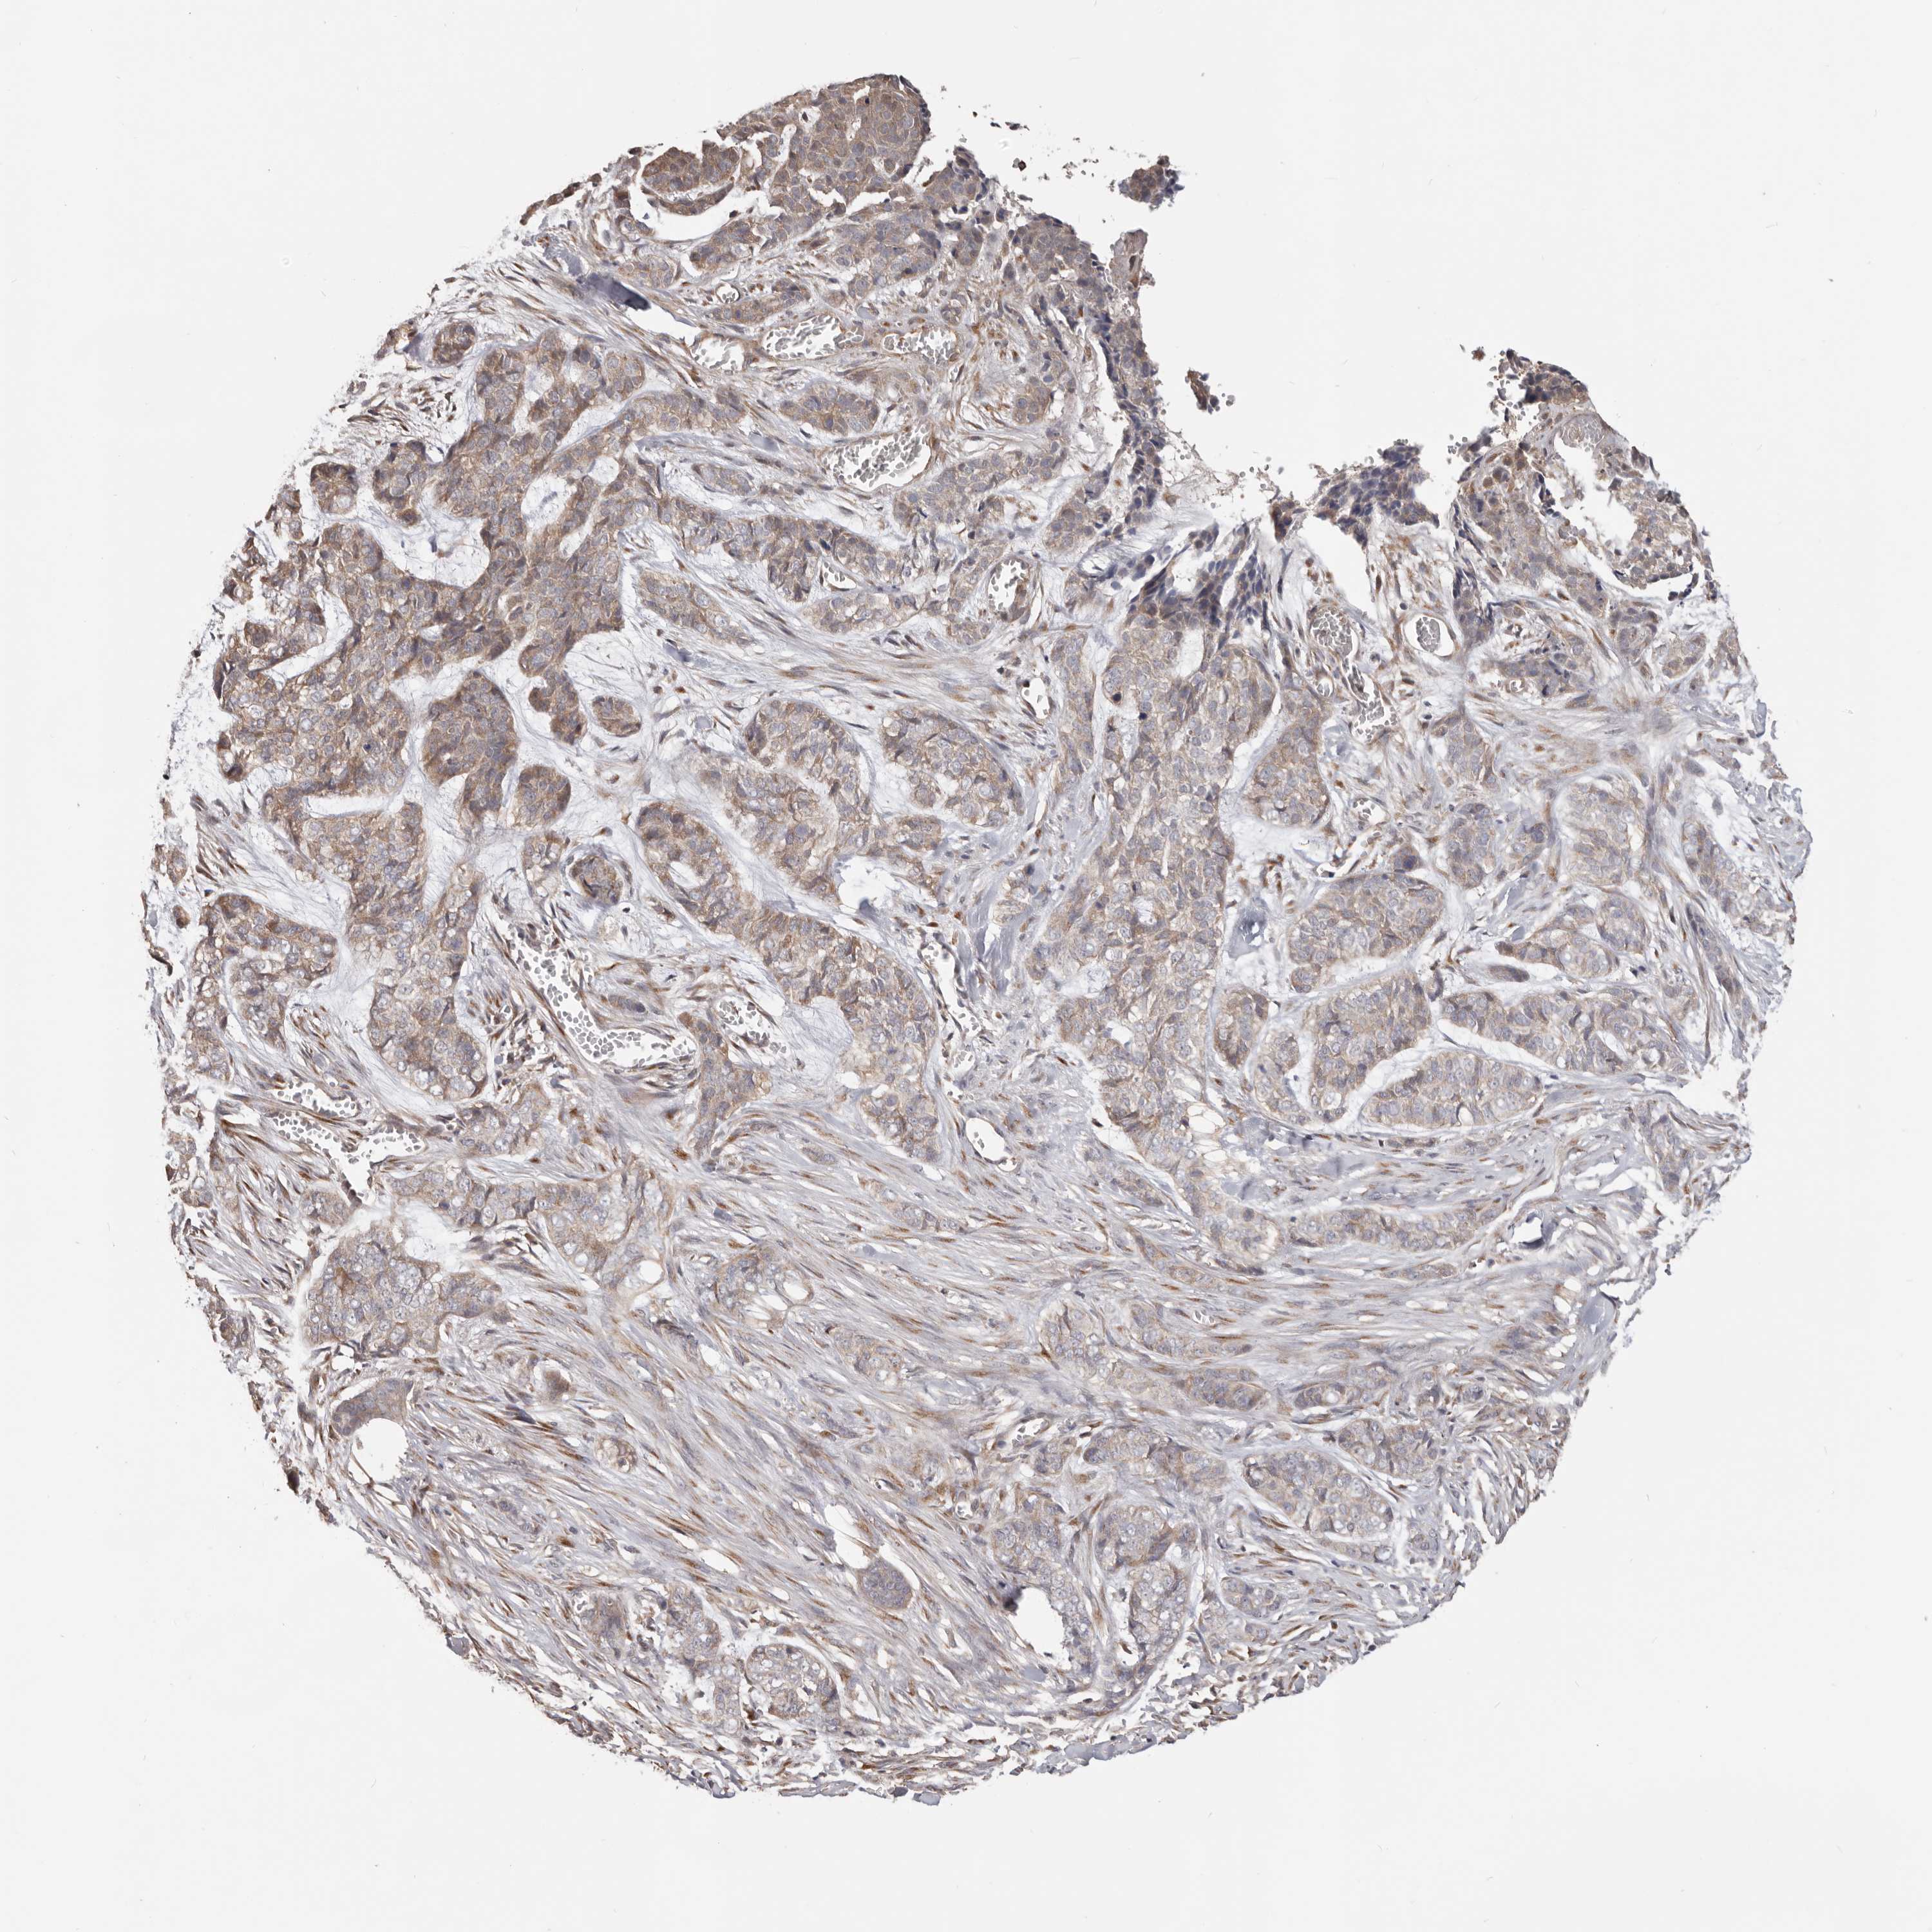

SKIN CANCER - Protein expressioni

A mouse-over function shows sample information and annotation data. Click on an image to view it in a full screen mode. Samples can be filtered based on level of antibody staining by selecting one or several of the following categories: high, medium, low and not detected. The assay and annotation is described here.

Each image is clickable and will lead to virtual microscopy that enables deeper exploration of all samples and also displays staining intensity scores, fraction scores and subcellular localization as well as patient and tissue information for each sample.

Antibody HPA029925

Basal cell carcinoma